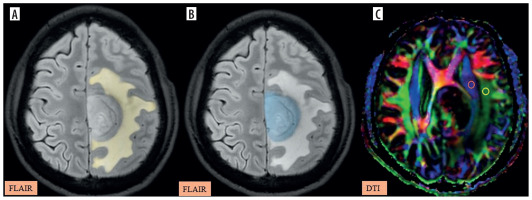

Figure 4

A-C) Patient with a low-grade glioma in the left frontal region presenting with headache and seizures. A) and B) Axial fluid-attenuated inversion recovery (FLAIR) images show the segmented peritumoral oedema (yellow) and tumour volume (blue). C) Image describing the calculation of the diffusion tensor image analysis along the perivascular space (DTI-ALPS) index using two regions of interest (ROIs) drawn within the projection (blue) and association (green) fibres in the left periventricular region